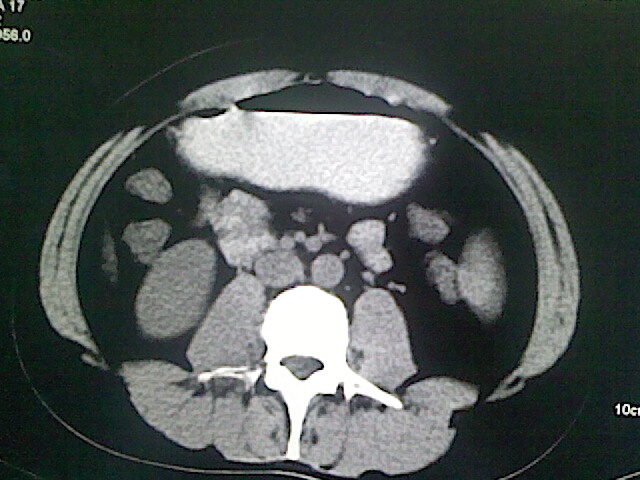

以下是引用卜一在2009-3-14 9:49:00的发言:[br]胆囊萎缩,胆囊壁不规则增厚,内部结构模糊,增强明显强化。另:肝左叶外侧段肝囊肿。支持:慢性胆囊炎!高度可疑:胆囊癌!

以下是引用余辉在2009-3-14 8:48:00的发言:[br]1)慢性胆囊炎。2)肝左叶外侧段肝囊肿。3)脂肪肝。[br]支持,胆囊萎缩,密度增高,不知b超具体有何提示,钙胆汁?结石?

以下是引用jiangjing在2009-3-14 10:18:00的发言:[br]1)慢性胆囊炎。2)肝左叶外侧段肝囊肿。3)脂肪肝。4.】建议行肝功能检查